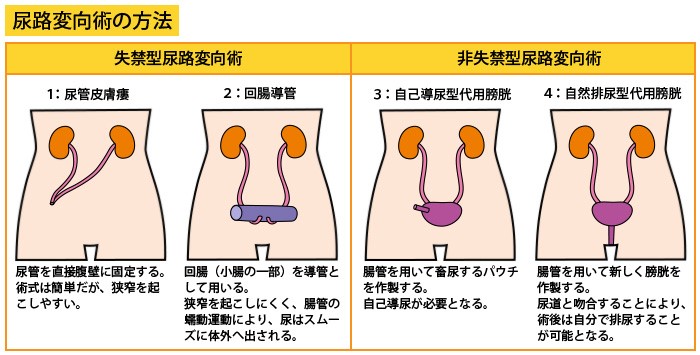

究める鏡視下膀胱全摘術・尿路変向術 Level up LRC, RARC | 三木。メジカルビュー社|泌尿器科|究める鏡視下膀胱全摘術・尿路変向。ロボット支援膀胱全摘除術(RARC) | 岩手医科大学 泌尿器科学講座。★3月精米★ 令和6年産 福井県産 いちほまれ 5kg 白米 精米。膀胱がん【泌尿器科疾患について】 - 東京慈恵会医科大学 泌尿器科。膀胱がん|KOMPAS。手術手技(膀胱全摘除術) | 領域情報 | アステラスメディカルネット。膀胱がん|KOMPAS。周術期の負担を軽減し早期社会復帰を!「ロボット支援腹腔鏡下。腎盂尿管移行部狭窄症に対するロボット支援腹腔鏡下腎盂形成術。朝倉書店『内科学』(第12版)デジタル付録。腹腔鏡下尿膜管摘出術及び左腎摘出術 - Olympus Professional。ロボット手術の定番!新品、未使用です。間違って2冊買ってしまったので、ページを開いてもいないため、本屋さんの「売上スリップ」も付いたままの全くの新品です。膀胱がんの外科治療について | 小野薬品 がん情報 一般向け。